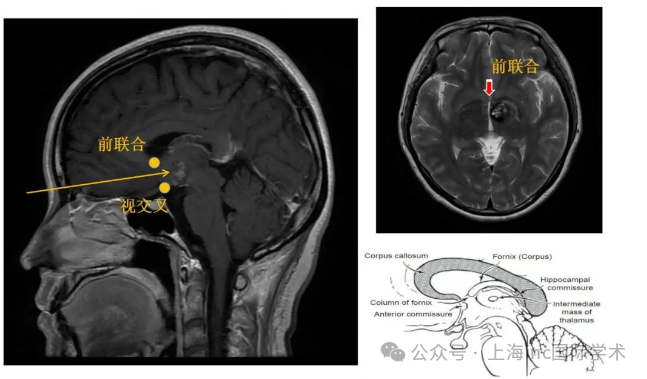

Kevin的海綿狀血管瘤正生長(zhǎng)在腦干中腦部位,這處于腦干上端,介于腦橋和間腦之間。人的中腦長(zhǎng)度約僅15~20mm。中腦是視覺以及聽覺的反射中樞。所有大腦皮層與脊髓間的上行及下行神經(jīng)通路都經(jīng)過(guò)中腦,同時(shí),中腦通過(guò)白質(zhì)與其他中樞神經(jīng)系統(tǒng)的分部相聯(lián)系,中腦的病變治療難度大,難以手術(shù),手術(shù)風(fēng)險(xiǎn)極大。但中腦海綿狀血管瘤與中腦膠質(zhì)瘤不同,其是良性病變,并且與正常腦組織有相對(duì)的界限。盡管手術(shù)難度很大,如選擇適合的手術(shù)入路并結(jié)合高超的顯微神經(jīng)外科手術(shù)技巧是可以全切腫瘤并獲得良好療效的。

腦干中腦部位的解剖結(jié)構(gòu)